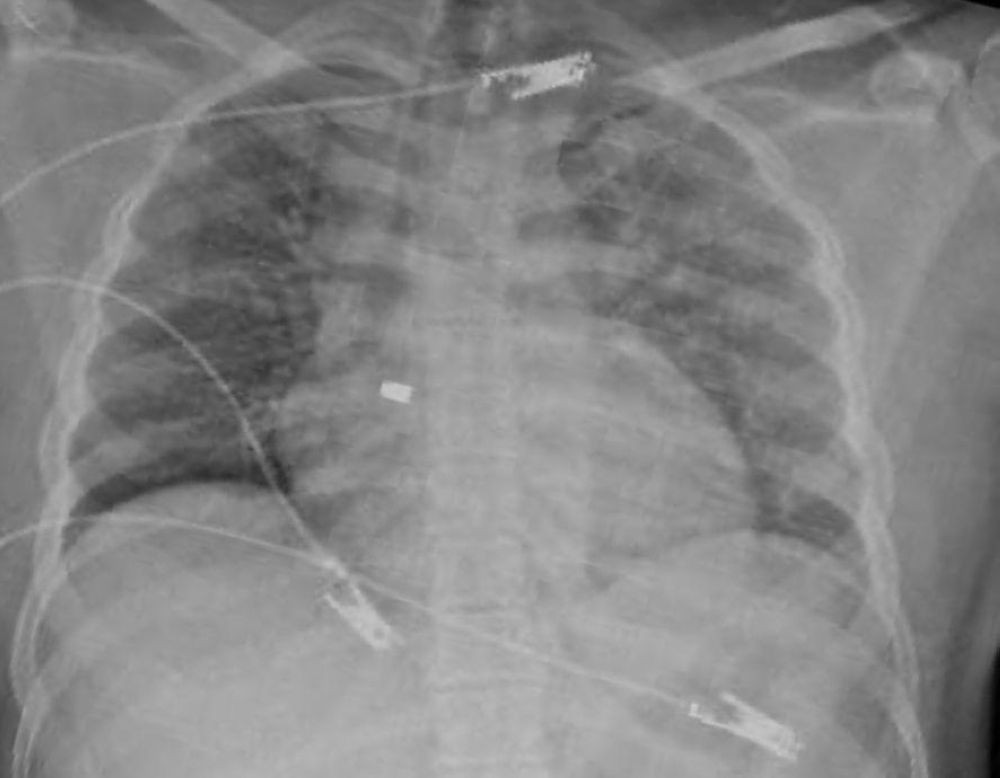

تمكن فريق مسار الإصابات بتجمع الرياض الصحي الأول من إنقاذ حياة مقيم؛ أصيب بطلقة نارية في منطقة الصدر.

وفي التفاصيل، وصل المصاب إلى مدينة الملك سعود الطبية، في حالة غير مستقرة مع هبوط في الدورة الدموية، وأكدت الأشعة الصوتية وجود تجمع دموي حول القلب؛ مما أدى إلى حدوث الإندحاس القلبي وشلل القلب عن ضخ الدم، وبقيادة استشاري جراحة الإصابات د. طارق السباحي؛ تم نقل المريض بشكل عاجل إلى غرفة العمليات وفتح الصدر وفتح تجويف التامور وإزالة الضغط حول القلب وإصلاح الإصابة في عضلة البطين الأيمن.

تمكنت الجهود الطبية من إعادة استقرار علامات المريض الحيوية، ليتم بعد ذلك التدخل من فريق جراحة القلب لدراسة وجود الرصاصة داخل القلب؛ حيث تبيّن إستقرار الرصاصة في الصمام ثلاثي الشفرات، ليقوم استشاريين جراحة القلب د. حمد الحبيب و د. محمد بكير بإجراء عملية قلب مفتوح للمصاب؛ تم خلالها إزالة الرصاصة بنجاح دون وجود أي مضاعفات، حيث غادر المريض المستشفى خلال أيام وهو بصحة جيدة -ولله الحمد-.